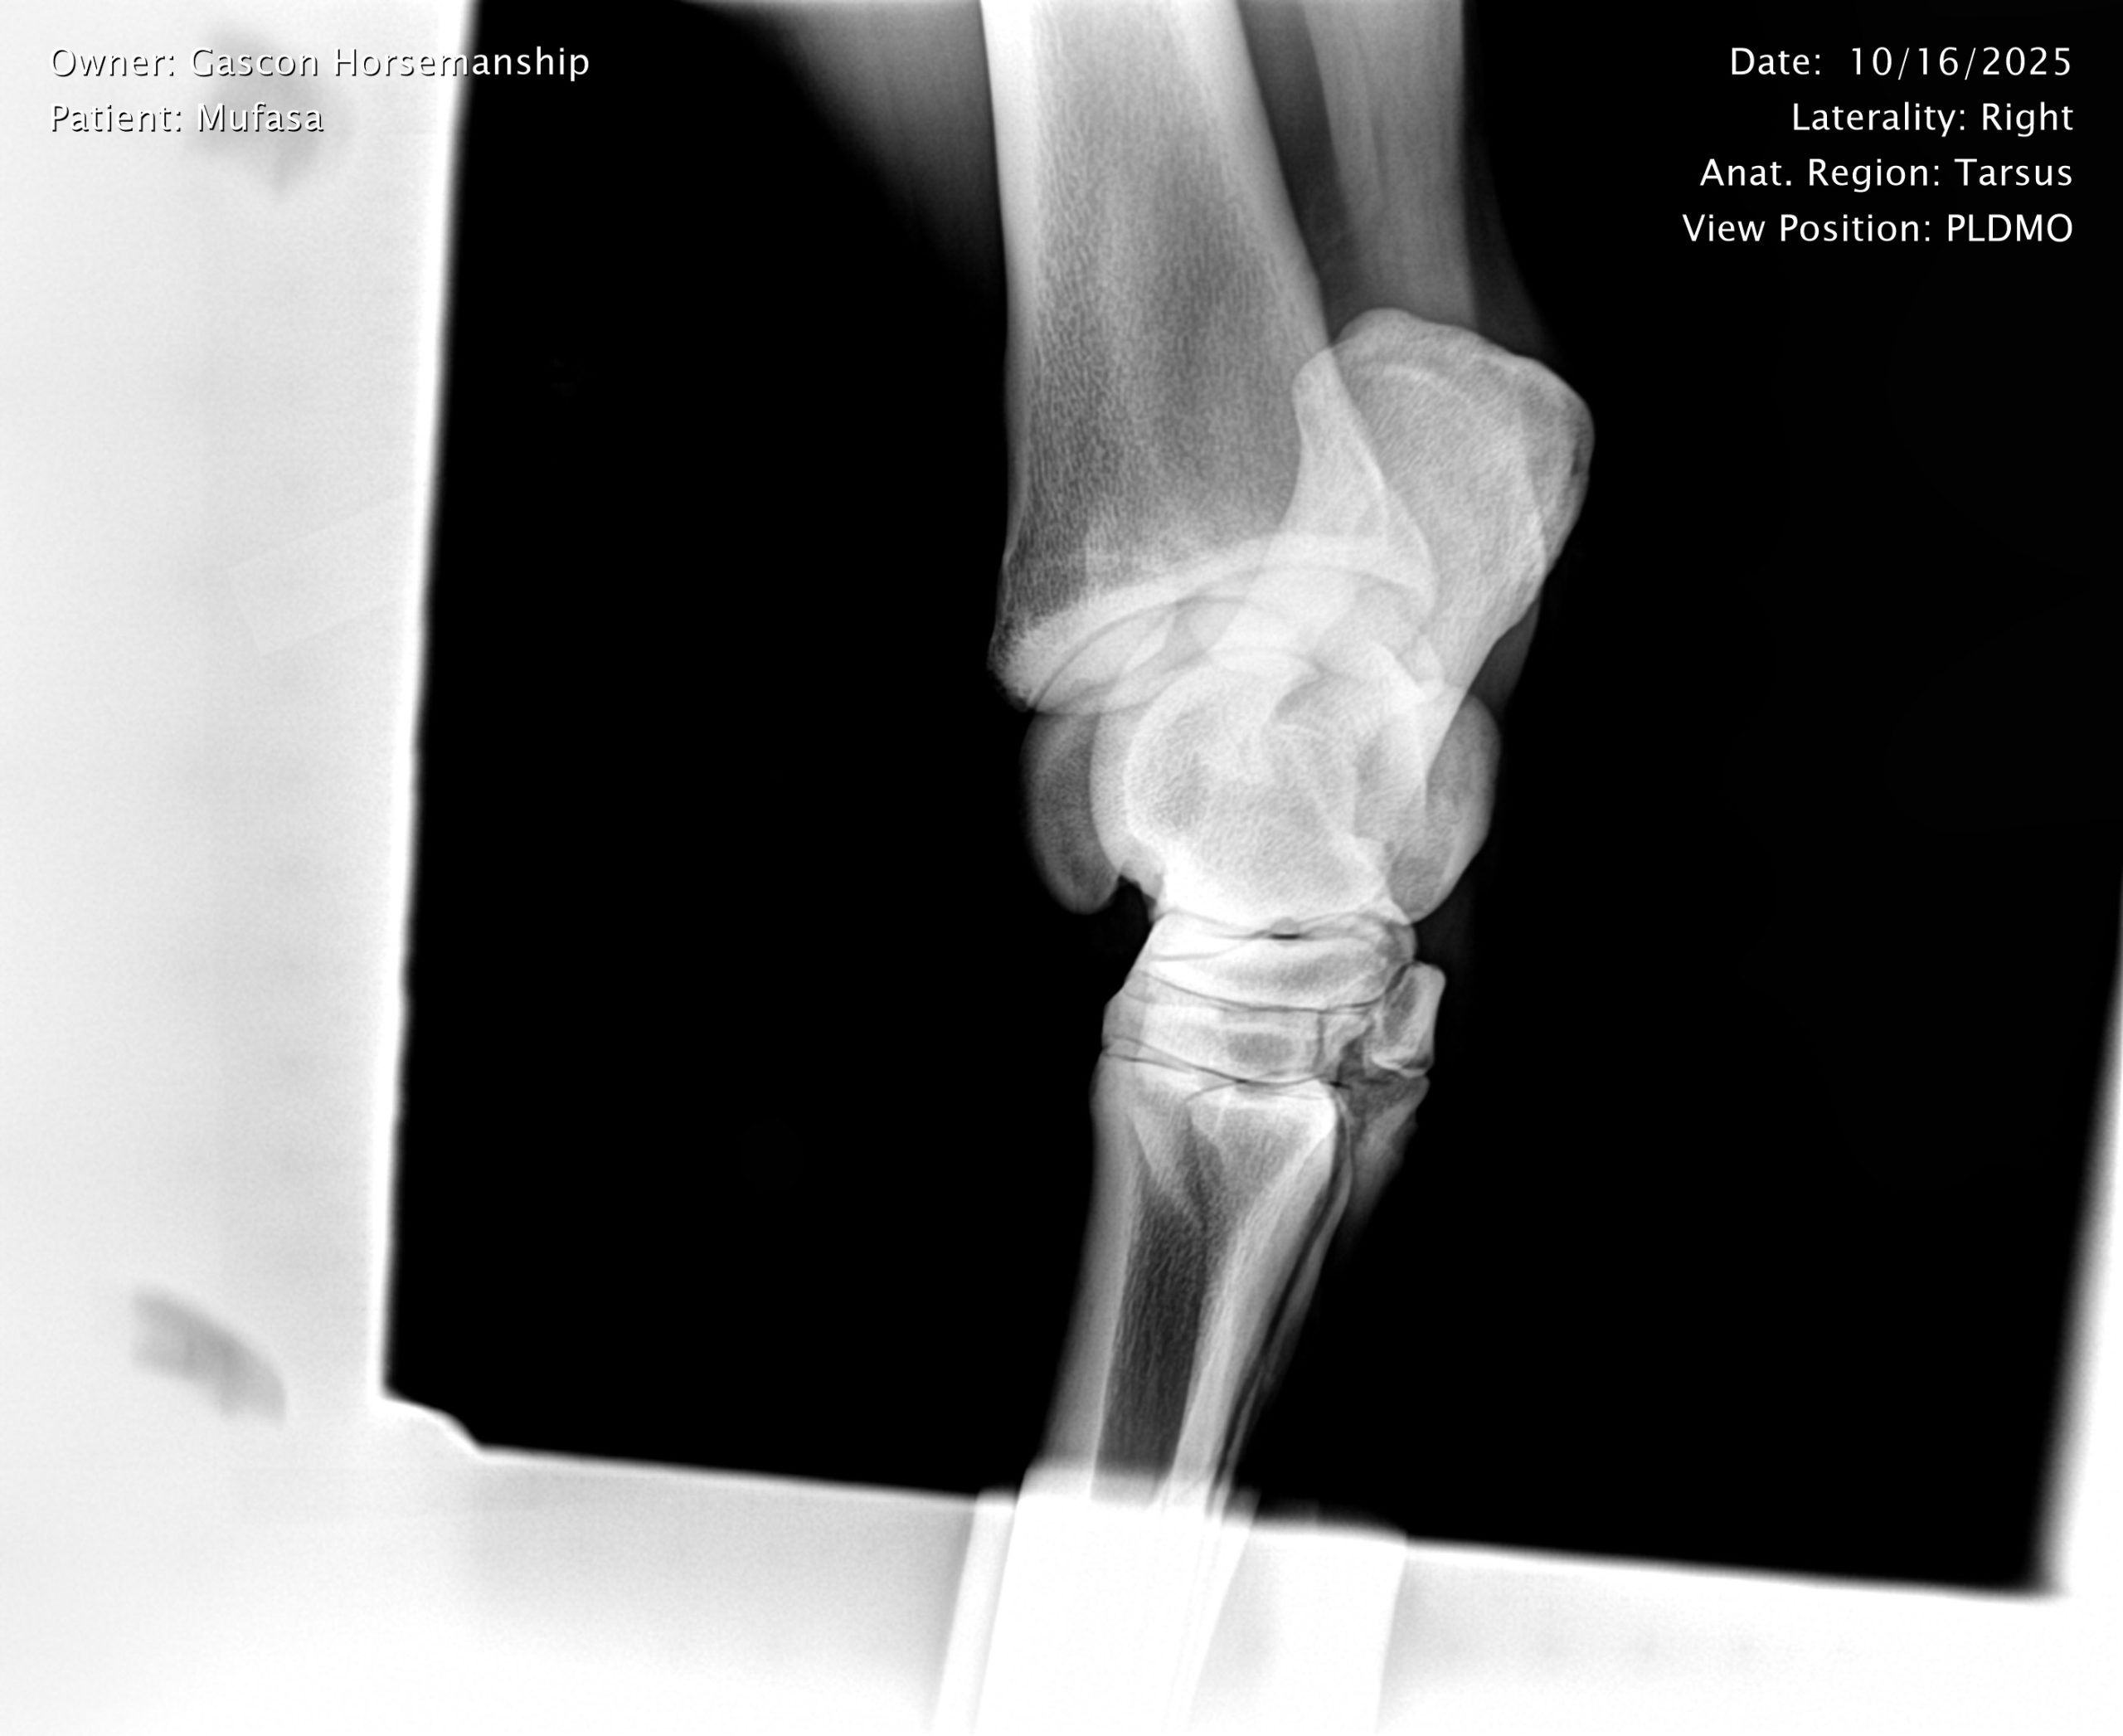

He already has a full pre-purchase exam on file, complete with 25 X-rays included in his album.